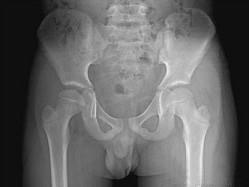

问题 男,8岁,右髋疼痛,活动受限,请结合图像,选出最可能的诊断 ( )

选项 A、退行性骨关节病 B、骨纤维异常增殖症 C、髋关节结核 D、剥脱性骨软骨炎 E、股骨头骨骺缺血坏死

答案 E